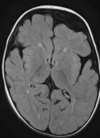

Esclerose mesial temporal

Observe a perda de volume, que indica atrofia e causa aumento secundário do corno temporal do ventrículo lateral.

O sinal alto no hipocampo reflete a gliose.

How well did you know this?